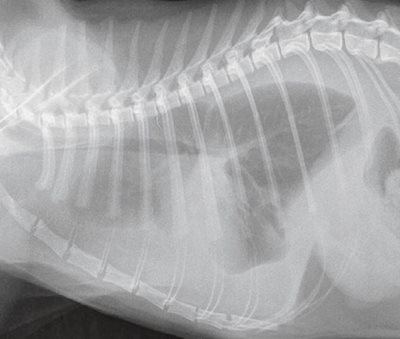

2. Radiographie de thorax, profil droit chez un chat présentant une cardiomyopathie hypertrophique. Épanchement pleural d’origine cardiaque. Le dosage du NT-proBNP sanguin, mais également du liquide d’épanchement, permet le diagnostic différentiel entre une origine cardiaque et une autre origine de l’épanchement. Chez ce chat, la valeur du NT-proBNP sanguin était supérieure à 1 500 pmol/l, confirmant l’origine cardiaque.

PHOTO : É. BOMASSI

Diagnostic différentiel entre origine cardiaque et origine non cardiaque d’un épanchement pleural chez le chat

Le NT-proBNP est utile pour le diagnostic étiologique différentiel d’un épanchement pleural d’origine cardiaque ou d’une autre origine (infectieuse ou tumorale, par exemple) (photo 2). Une valeur supérieure au seuil de 258 pmol/l (Se et Sp non fournies) permet d’orienter l’épanchement pleural vers une origine cardiaque [15].

Une autre étude indique une valeur seuil proche de 214 pmol/l (Se de 86,4 % et Sp de 88,9 %) pour le NTproBNP sanguin, et une valeur seuil de 322 pmol/l (Se de 100 % et Sp de 94,4 %) pour le dosage du NT-proBNP directement sur le liquide d’épanchement pleural [17].